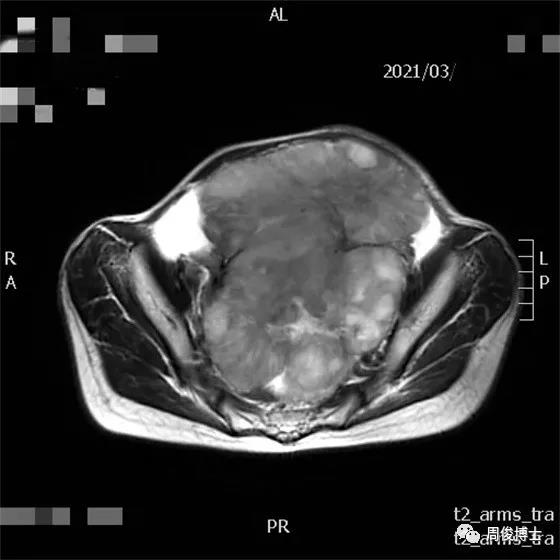

治療一個半月后,腫瘤退縮,腹水消失,大腸形態(tài)恢復(fù),可見腸內(nèi)容物。